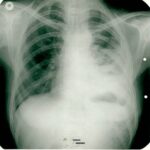

1995 yılında küçük hücreli anaplastik karsinom teşhisi konulan 31 yaşındaki erkek hasta, kemoterapiyi reddederek immünomodülatör tedavi ile 7 ayda tam iyileşme sağladı. Şiddetli ağrıları sadece 12 günde kayboldu ve röntgende tümör tamamen ortadan kalktı.

1995: 31 yaşındaki erkek hasta öksürük, ateş ve sırt ağrısı ile başvurdu.

Biyopsi sonucu "küçük hücreli anaplastik karsinom" teşhisi kondu.

Röntgende kitle küçülmüş durumda görüldü.

Röntgen tümörün tamamen kaybolduğunu gösterdi.

Radyolojik Kanıt: Röntgende tümör tamamen kayboldu